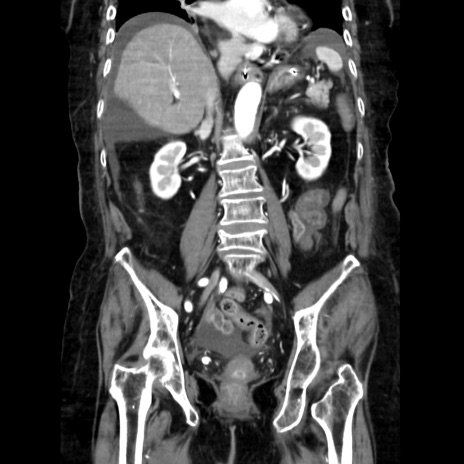

症例40(冠状断像)

【症例】90歳代女性

【主訴】腹痛・嘔吐

【現病歴】 食欲低下、嘔吐があり昨日他院受診。肺炎と診断され入院となる。入院後より腹部全体に圧痛あり。胃管留置され経過みていたが、症状持続するため、

当院転院となる。

【既往歴】胸椎圧迫骨折、胆石症

【身体所見】腹部:中央に激痛あり、圧痛あり、反跳痛不明

【データ】WBC 17100、CRP 18.82

冠状断像